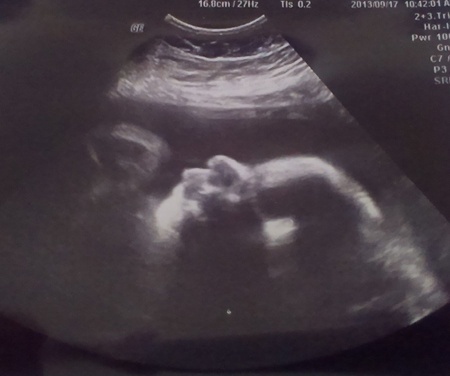

A héten megvolt az utolsó kötelező 38. heti ultrahang, egy CTG-vel karöltve. Az ultrahangon mondtak jót is és kevésbé jót is, de tudom, hogy rengetegen nyugtattok, a vesetágulat elmúlhat, csak megfigyelés szükséges. Sajnos a tágulat nőtt Koppánnyal együtt, így elérte a 9 mm-t mindkét oldalon. Viszont Babócám szépen fejlődik és 38+2-nél már 3229 gramm és a fejméretre sem panaszkodhatom, hiszen 93 milliméter. A méhlepényem készül a nagy napra, ahogy érzem a testem többi részével együtt.